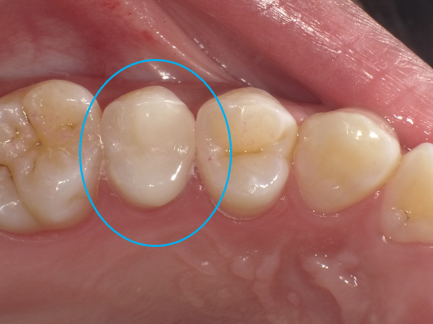

「神経を抜く」と言われた歯を残した症例|つくば市のセカンドオピニオン・セレック治療(30代女性)

| 主訴 | 虫歯治療の相談。他院で「神経を抜く」と言われたが、可能であれば神経を残して治療したい。 |

|---|---|

| 診断名 | 深い虫歯(象牙質う蝕・C2) |

| 年齢・性別 | 30代 女性 |

| 治療期間・回数 | 1日・1回 |

| 治療方法 | セレックシステムによる精密セラミック修復(神経の保護を含む) |

| 費用 | 88,000円(税込96,800円) |

| メリット | ・最短1日で治療が終わり、お仕事等で忙しい方でも通いやすい ・削った直後に封鎖するため、細菌感染を防ぎ神経を残せる可能性が格段に高まる ・接着力が高いため、再発(二次虫歯)のリスクを低減できる |

| デメリット・注意点 | ・保険外診療のため費用が高くなる ・歯ぎしりや食いしばりにより、稀に欠ける可能性がある ・術後に痛みが出た場合は、再治療(神経の処置)が必要になる場合がある |

| 備考 |